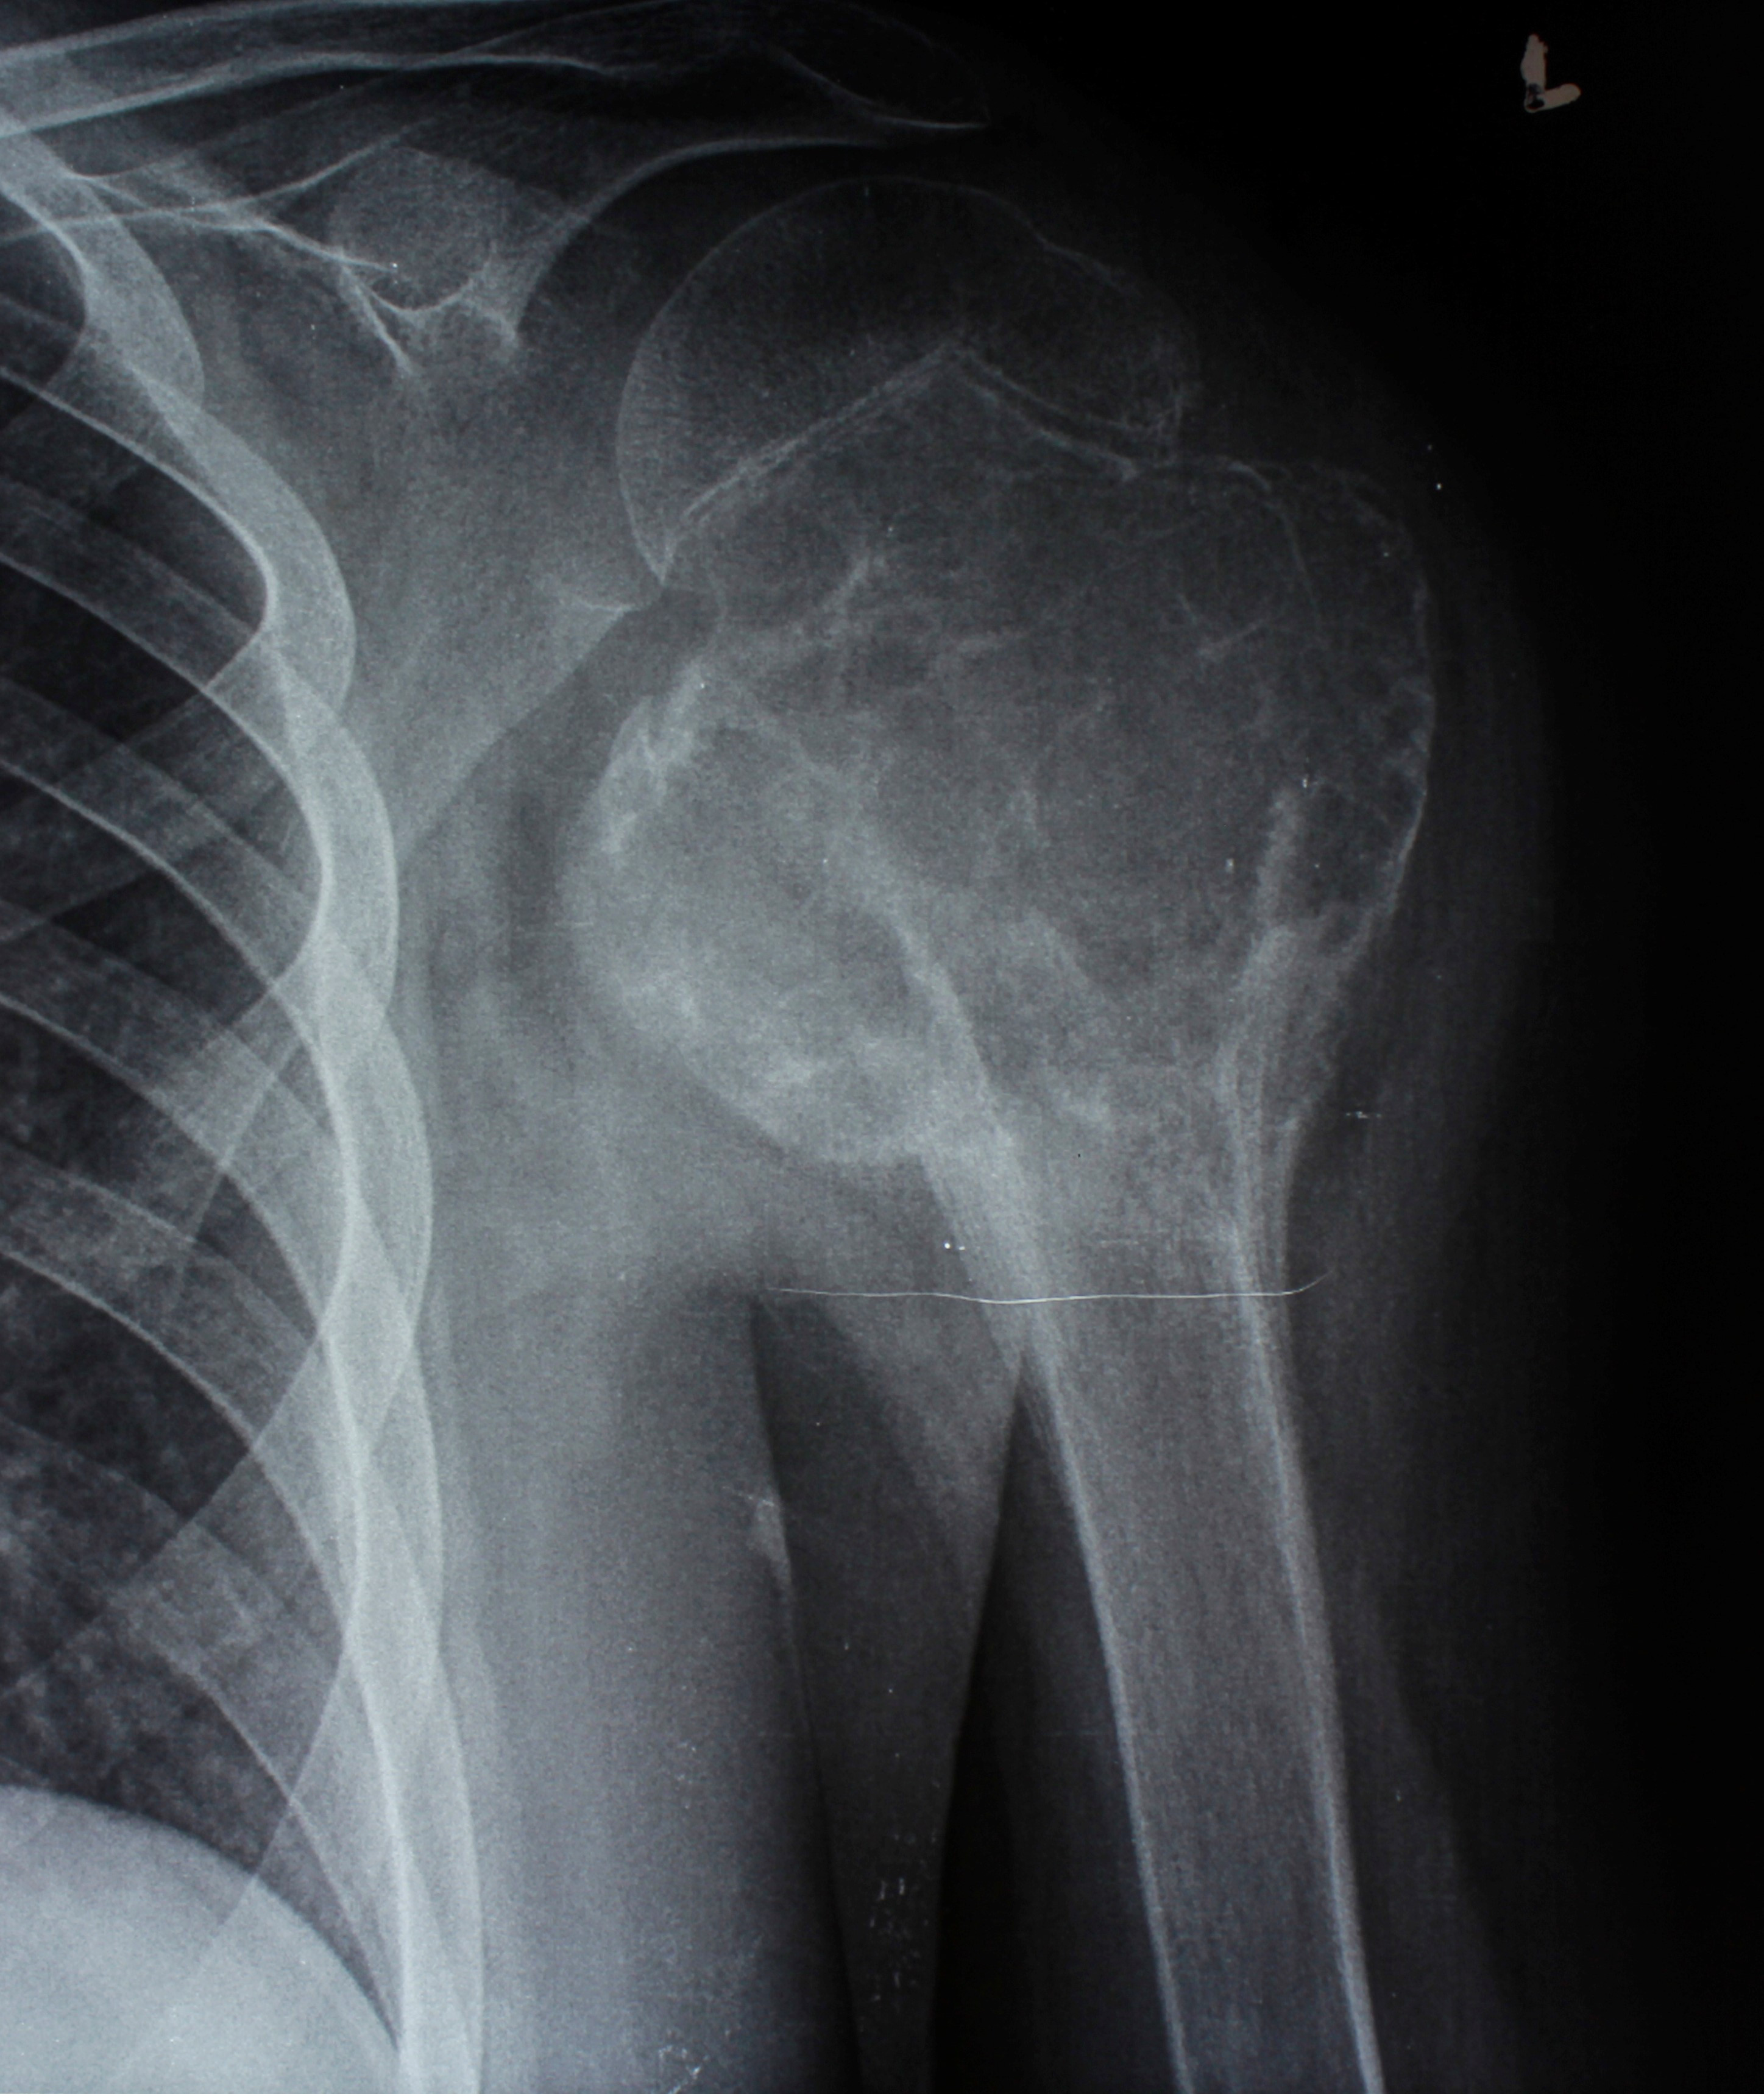

4. Гигантоклеточная опухоль верхней трети плечевой кости

У 14-летнего ребенка был литический вариант гигантоклеточной опухоли с выраженным мягкотканным компонентом, врастающим в подмышечную клетчатку и дельтовидную мышцу. Произведено удаление опухоли путем резекции верхней части плечевой кости, образовавшийся дефект был восстановлен металло-цементным спейсером. Этот метод позволяет оперировать больных с костными опухолями в максимально краткие сроки, во избежание прогрессирования заболевания.

До операции